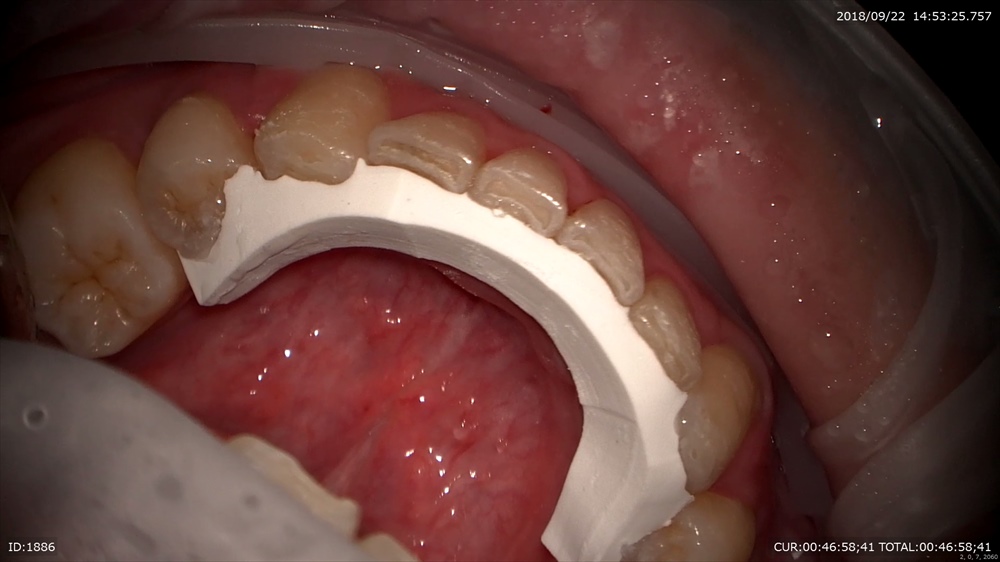

矯正が終わるとリテーナーといって後戻り防止装置をつけます。

装置除去。ガタガタの歯並びは綺麗になりました。2年かかりました。抜歯症例。

EXTARO300ここまで広範囲に。しかも直視で上顎が見えます。これマイクロを使用している先生がみたら私の言いたい事が解ると思います。

下顎も見える!!